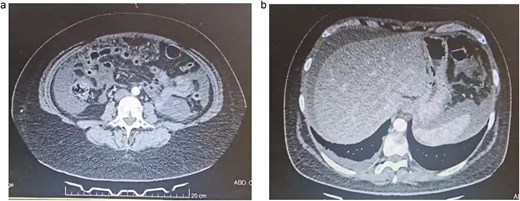

Due to this, a contrast-enhanced computed tomography (CT) was requested to help in the diagnosis. It revealed 1000 cc of free liquid in her abdomen and inflammation of the peritoneum with diffuse peritoneal thickening and right pleural effusion (Fig. 1a and b).

(a) Abdominal CT, multiple bowel loops are seen surrounded by liquid. (b) Abdominal CT, thickening of the peritoneum is seen with free liquid.